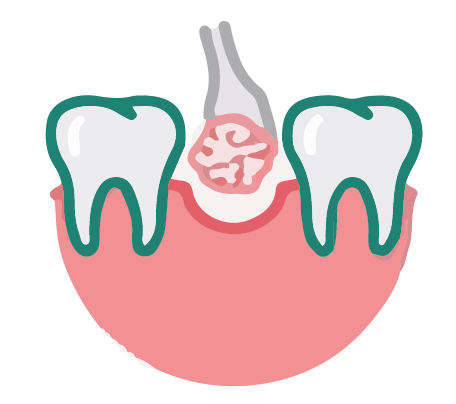

補骨手術是為了在植牙前幫牙齒打好地基,也就是「補骨粉」,其原理是利用人工骨粉或骨塊置入齒槽骨中,讓自體的骨質細胞沿著生長,使齒槽骨能生長完整。補骨手術填入骨粉後,能促使骨頭再生,待齒槽骨恢復穩固後,就能植入植體,讓植牙能更穩固,也能延長壽命。

簡單的補骨手術,會在骨缺損處填入骨粉、骨塊等材料,再覆蓋上再生膜,隔絕外界刺激,最後縫合,僅需局部麻醉,約30分鐘即可完成。

將人工骨粉或是骨塊,置入齒槽骨,補骨粉會建立一個架構,讓自體骨質細胞沿著生長。齒槽骨萎縮嚴重者,須等待骨頭新生完整,才能進行植牙;輕微者,植牙、補骨可同時進行。

STEP 3

開始補骨粉

在需要補骨粉的牙齦位置,將牙齦切開,確認需要補骨粉的位置與大小後,在齒槽骨萎縮處,填入適量骨粉,讓自體骨質細胞可以沿著生長。